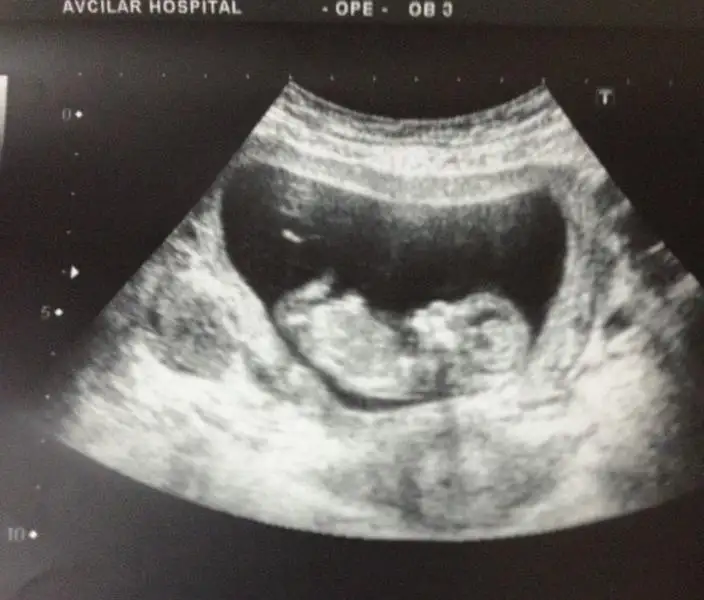

kızlar tecrübeli arkadaşlardan yorum rica ediyorum. doktorum%85-90 erkek dedi. henüz 12. haftamdayım. $2014-02-12 18.18.41.webp

şimdiden teşekkür ederim..

kızlar tecrübeli arkadaşlardan yorum rica ediyorum. doktorum%85-90 erkek dedi. henüz 12. haftamdayım. Eki Görüntüle 977889